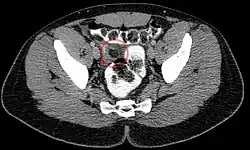

Abdominal CT scan, Epiploic Appendagitis (circle)

The condition commonly occurs in patients in their 40s and 50s predominantly in men. Epiploic appendagitis is normally misdiagnosed in most patients.[2] Epiploic appendagitis presents with an acute onset of pain, commonly in the left lower quadrant the symptoms often lead to a misdiagnosis for diverticulitis. Diverticulitis manifests with evenly distributed lower abdominal pain accompanied with nausea, fever, and leukocytosis. Patients with acute epiploic appendagitis do not normally report a change in bowel habits, while a small number may have constipation or diarrhea.[2]

Ultrasound and CT scans are the normal means of positive diagnosis of epiploic appendagitis. Ultrasound scans show "an oval, non-compressible hyperechoic mass with a subtle hypoechoic rim directly under the site of maximum tenderness".[4] Normally, epiploic appendages cannot be seen on CT scan.[4] After cross-sectional imaging and the increased use of abdominal CT for evaluating lower abdominal pain, EA is increasingly diagnosed. Pathognomonic CT scan data represent EA as 2–4 cm, oval shaped, fat density lesions, surrounded by inflammation. Contrasting with diverticulitis findings, the colonic wall is mostly unchanged.